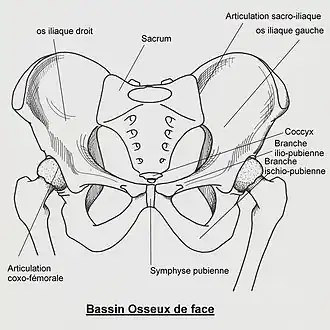

Le pubis (ou os pubis) est la partie antérieure et inférieure de l'os coxal.

Le pubis est relié en haut à l'ilium via l'acétabulum et en arrière à l'ischium en formant la branche ischio-pubienne.

On lui décrit trois parties : le corps, la branche supérieure et la branche inférieure du pubis[1].

Sa face médiale présente la surface symphysaire qui s'unit à son équivalent du pubis opposé pour former la symphyse pubienne.

A l'avant se projette le tubercule pubien sur lequel s’insère le ligament inguinal.

Sur son bord supérieur se présente la crête pubienne.

Son bord postérieur limite en avant le foramen obturé.

La branche supérieure du pubis (ou branche horizontale du pubis) s'étend latéralement et en haut du corps du pubis à l'acétabulum.

Il forme le bord supérieur du foramen obturé qui présente au niveau de l'incisure de l'acétabulum le tubercule obturateur postérieur ou tubercule ischio-pubien postérieur..

Le bord supérieur forme le pecten du pubis qui prolonge la ligne arquée de l'ilion. Il donne insertion en avant au muscle pectiné et en arrière sur son versant médial au muscle petit psoas.

Sur son bord antérieur et au niveau de la jonction entre le pubis et l'ilium, se présente l'éminence iliopubienne.

Son bord inférieur forme la crête obturatrice qui forme la lèvre antérieure du sillon obturateur (ou gouttière sous-pubienne).

La branche inférieure du pubis (ou branche descendante du pubis) prolonge en bas et en arrière pour rejoindre la branche de l'ischion pour former la branche ischio-pubienne. Elle forme le bord antérieur et inférieur du foramen obturé qui présente dans sa partie moyenne le tubercule obturateur antérieur ou tubercule ischio-pubien antérieur.

Mammifères

Le pubis est la partie inféro-ventrale de l'os iliaque. Pièce osseuse composée de deux os et constituant la partie antérieure et inférieure de l'os iliaque (os large et plat qui forme le bassin). L'articulation sur la ligne médiane des deux os pubiens s'appelle la symphyse pubienne[3].